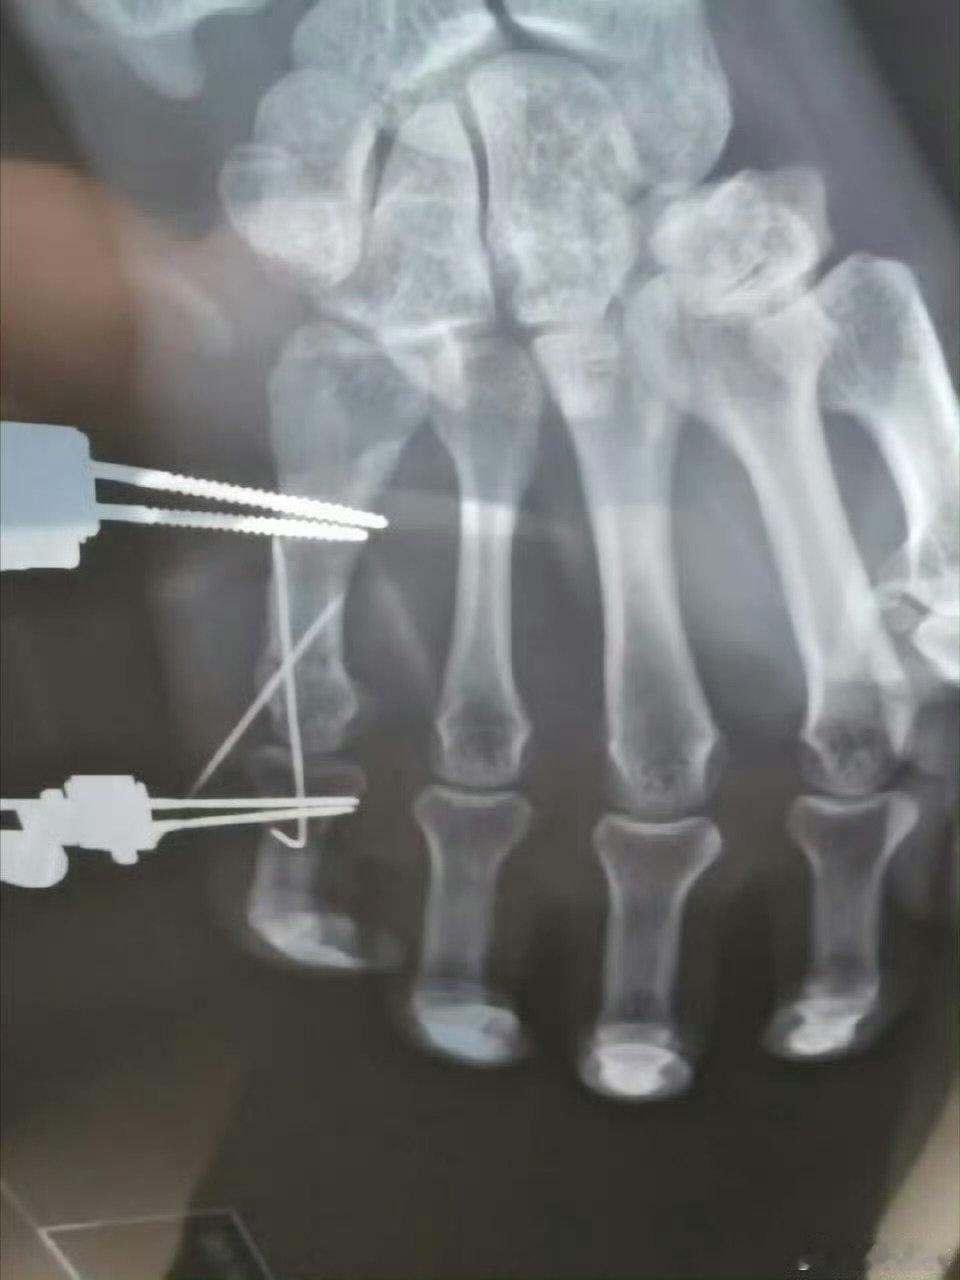

成毅天地剑心的第一个受害者出现 ,天地剑心的第一个受害者出现成毅打戏确实精彩,但专业动作请勿模仿啊! ​​​